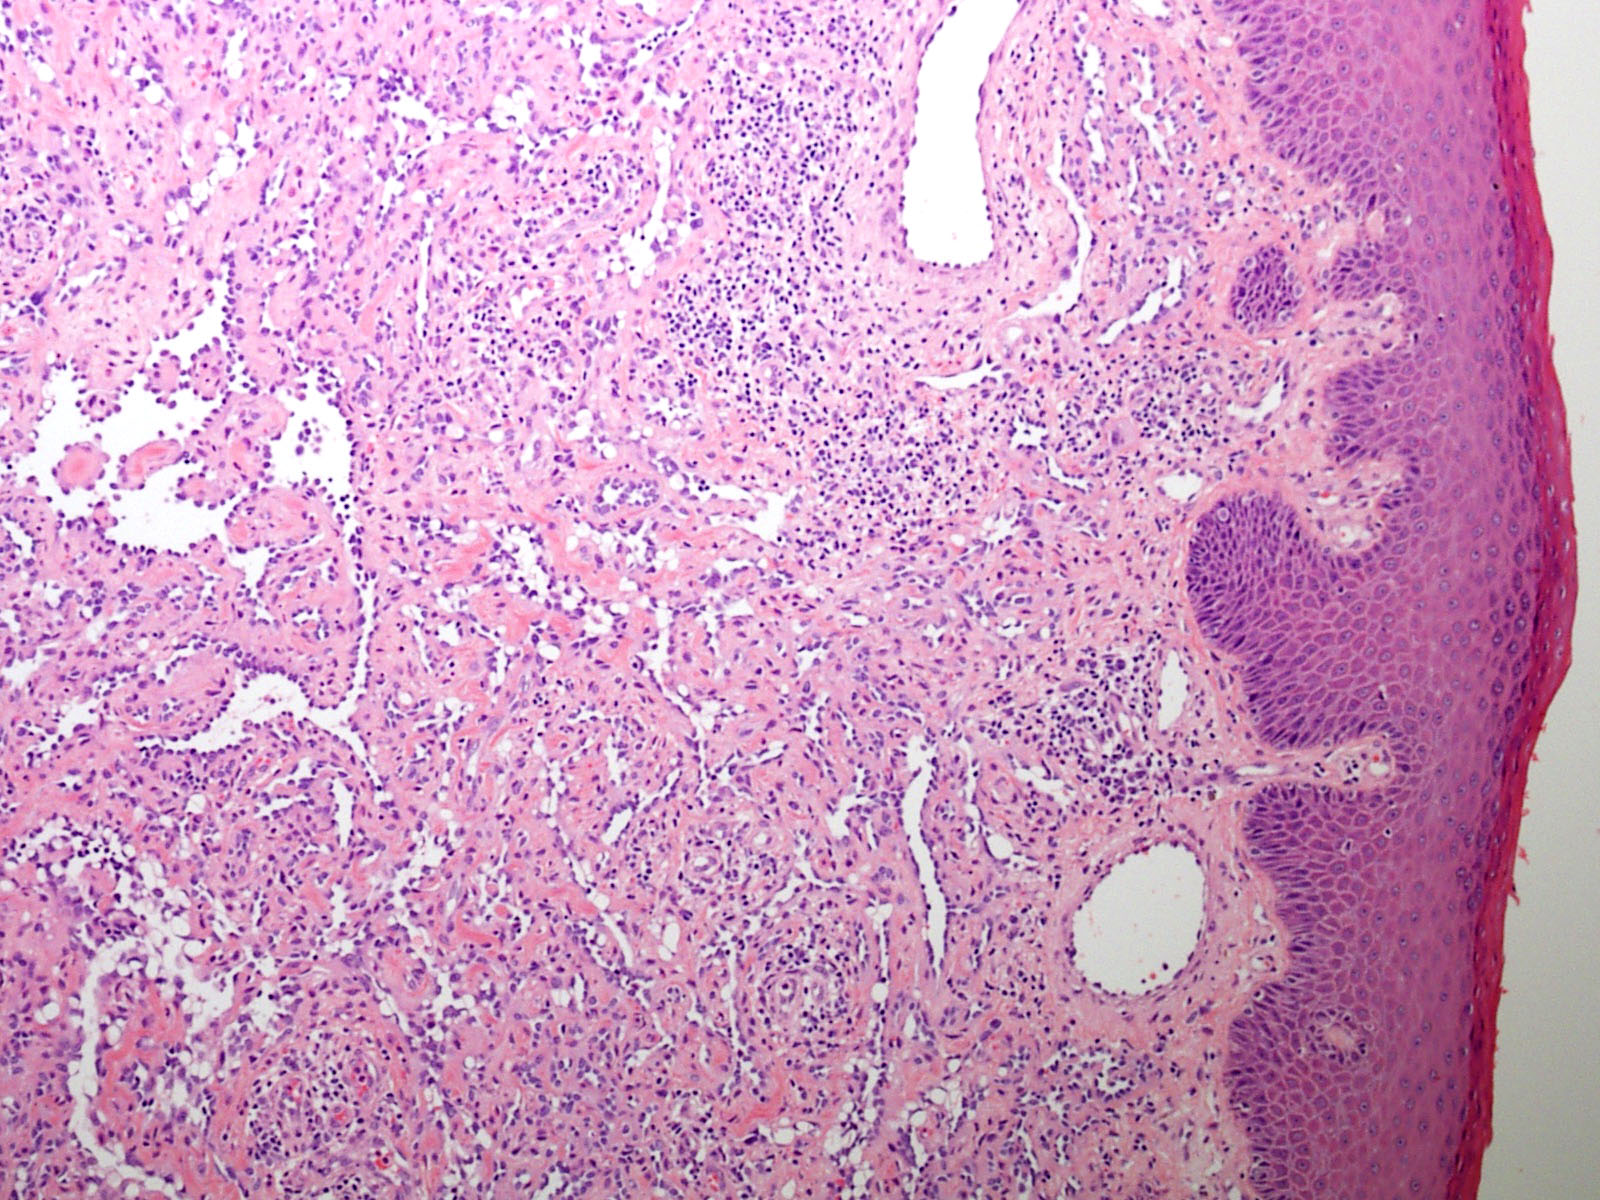

Microscopic (histologic) description

- Poorly circumscribed lesion, infiltrating dermis and subcutis with dissecting planes (Int J Clin Exp Pathol 2010;3:528)

- Composed of elongated arborizing vascular channels that resemble rete testis, hence the name

- Endothelial cells are bland with hobnailed hyperchromatic nuclei

- Nuclear atypia is not seen

- Mitotic figures are rare

- Lesional stroma is fibrotic and shows lymphoid infiltrate (J Med Case Rep 2021;15:69, Int J Clin Exp Pathol 2010;3:528)

- Occasional solid growth may be seen (Stockman: Diagnostic Pathology - Vascular, 1st Edition, 2015)

- In the dermis, vessels may become ectatic and lose retiform appearance

- Occasional cells with cytoplasmic lumina may be rarely seen (J Med Case Rep 2021;15:69)

- Occasionally, intraluminal papillary proliferation may be seen, resembling Dabska tumor (Hornick: Practical Soft Tissue Pathology - A Diagnostic Approach, 2nd Edition, 2018)

- May arise as a retiform component in a composite hemangioendothelioma (Surg Case Rep 2021;7:249)

- Lacks adjacent areas resembling lymphangioma, seen in other types of hemangioendothelioma, such as Dabska tumor (Weiss: Enzinger and Weiss's Soft Tissue Tumors, 7th Edition, 2019)

Microscopic (histologic) images

A 30 year old man presents with a red to purple plaque involving the right thigh. A punch biopsy through the lesion shows light microscopic features as depicted in the photomicrograph above. Which of the following is the most likely diagnosis in this case?

E. Retiform hemangioendothelioma. The photomicrograph shows a vascular lesion with retiform vessels lined by a single layer of endothelial cells with hobnailing. A lymphoid aggregate is also present. Answers B - D are incorrect because other characteristic essential features of any of the given options, except atypical vascular lesion, are not seen here. Answer A is incorrect because the clinical scenario is not appropriate for a diagnosis of atypical vascular lesion. Therefore, the correct diagnosis is retiform hemangioendothelioma.